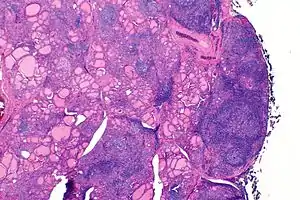

Tiroidite de Hashimoto

Tiroidite de Hashimoto é uma doença autoimune em que a glândula tiroide vai sendo gradualmente destruída.[1][6] No início da doença podem-se não manifestar sintomas.[1] Ao longo do tempo, a tiroide pode ir aumentando de volume, formando um bócio indolor.[1] Algumas pessoas desenvolvem hipotiroidismo, que se manifesta por sintomas como aumento de peso, fadiga, obstipação, depressão e dores generalizadas.[1] Após vários anos, a tiroide geralmente diminui de volume.[1] Entre as possíveis complicações está o linfoma da tiroide.[2]